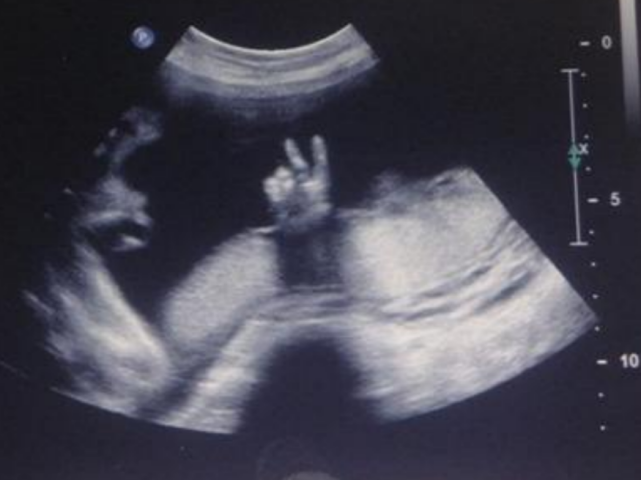

后面的胚胎发育过程也只能通过B超、MRI等方式间接观察,在细胞水平直接观察胚胎发育的动态过程仍属空白。

只有妇产科医生能看懂的胎儿超声